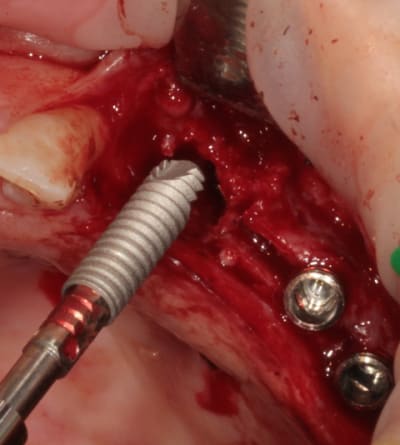

après les implants lisses coniques il faut passer aux lisses Axioms

donc Ostéotomes impactés pour mettre la corticale du sinus aux dimensions et pousser la membrane (et l'éponge)

en 25 pour le moment l'axiom lisse est de 3.4mm

puis les Axioms avec un 4 mm en 25

retouche de l'os avec le D1 (face plane)

contrôle de l'os vestibulaire (différents contraste pour juger de la "minceur" de l'os :-)))